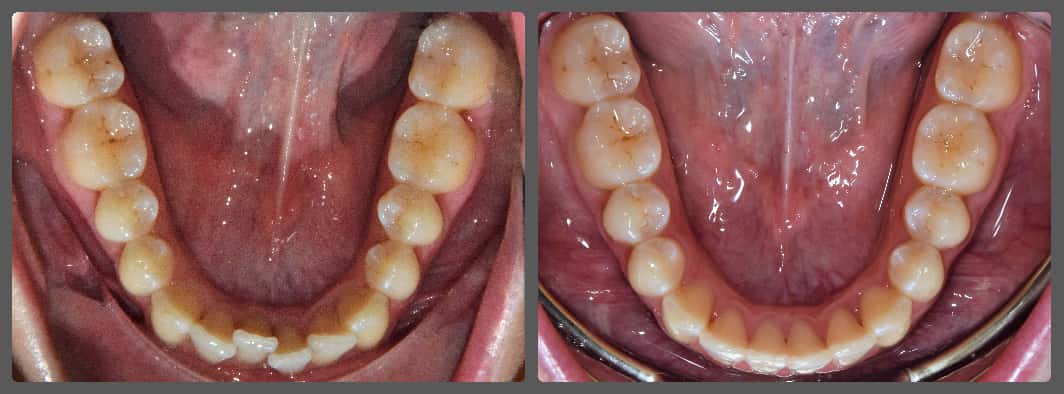

Balázs súlyos alsó torlódása miatt keresett fel magánrendelésemen. A diagnosztikus vizsgálatok során előbbin túl alsó-felső fogívszűkületet, valamint nyitott harapási hajlamot állapítottam meg. Kezelését Pitts21 alsó-felső rögzített fogszabályozó készülékkel kezdtük meg. A nyitott harapási hajlamot a hátsó fogakra helyezett harapásemelővel kontrolláltuk. A torlódott fogaknak tolórugóval és interproximális redukcióval teremtettünk helyet, és intermaxilláris gumihúzással tökéletesítettük a harapást. A fogszabályzó kezelés teljes időtartama alatt Balázs 110%-osan együttműködő volt, ezért 21 hónap alatt sikerült kiemelkedő végeredményt elérnünk.